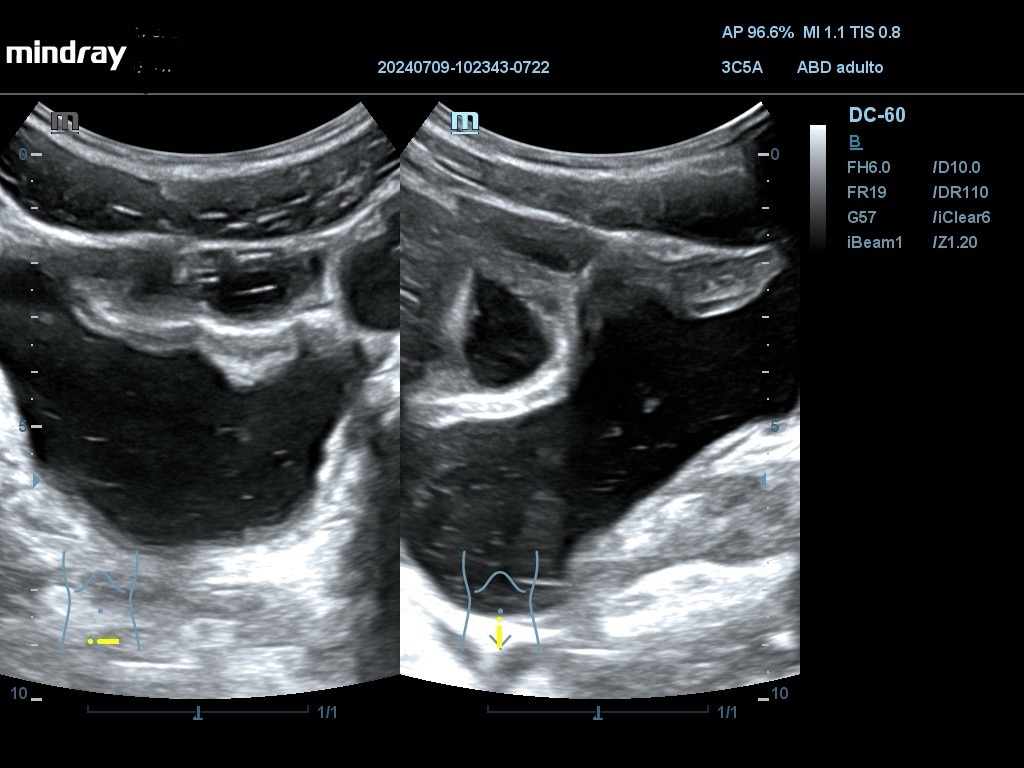

Ecografía: Se han observado varias imágenes poco habituales en vejiga urinaria: imágenes hiperecogénicas flotantes sin sombra posterior, móviles (detritus), engrosamiento de pared vesical que simula una vejiga no distendida con áreas anecoicas, pared con imagen en doble carril, masa vesical.

La sospecha inicial por criterios epidemiológicos es esquistosomiasis con afectación de vejiga urinaria. El diagnóstico diferencial se debe hacer con otras infecciones y tumores (raros en esta edad). En uno de los casos, AE considera que las imágenes se deben a vejiga poco replecionada y no las valora como patológicas. La masa vesical podría ser de tipo inflamatorio o tumoral.

Nuevos pacientes, con riesgo de enfermedades poco prevalentes en su nuevo medio, nos exige valorar hallazgos de otra manera. Los hallazgos de estos pacientes cubren un rango amplio de hallazgos probables en pacientes con esquistosomiasis con afectación de vejiga urinaria, que debe ser la primera sospecha en pacientes con hematuria procedentes del África subsahariana.